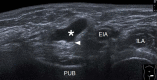

Inguinal hernia is the most prevalent type of abdominal wall hernia. Indirect inguinal hernia is twice as common as direct inguinal hernia. Computed tomography and magnetic resonance imaging can be used to evaluate inguinal hernia, but these modalities are greatly limited by their cost and availability. Ultrasonography has emerged as the most convenient imaging tool for diagnosing inguinal hernia due to its advantages, such as portability and absence of radiation. The present pictorial review presents an overview on the use of ultrasonography in the evaluation of inguinal hernia with a particular emphasis on the regional anatomy, relevant scanning tips, identification of subtypes, postoperative follow-up, and diagnosis of pathologies mimicking inguinal hernia.